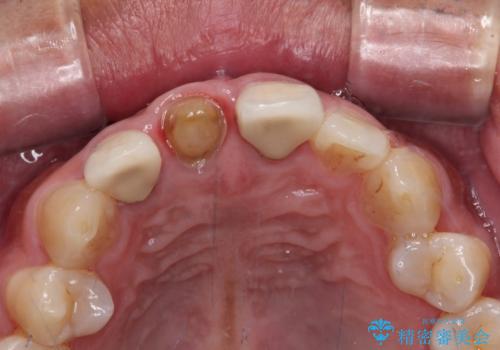

- 前歯の変色した歯を治したいことを主訴として来院された患者様です。

数年前、外傷により両隣の歯とともに根管治療を行い、その後両隣の歯はオールセラミッククラウンにて補綴したそうです。

時間の経過とともに、セラミックにしなかった当該歯の変色が目立つようになり、オールセラミッククラウンにて補綴することとしました。